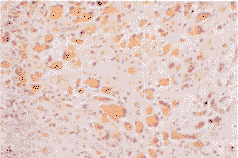

二、uPA免疫组化染色显示 uPA蛋白与uPA mRNA表达一致,主要分布在GBM、AA组织的肿瘤细胞及血管内皮细胞,定位于细胞浆(见插页第4页图4),LGG及正常脑组织则较少。

图4 多型性胶质母细胞瘤UPA表达,阳性产物定位于肿瘤细胞胞浆(ABC法宝×200)